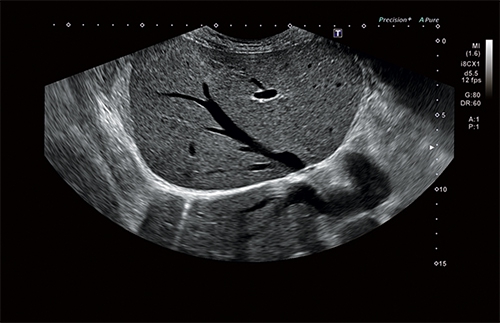

Ультразвуковая система Aplio i700 обеспечивает лучшее качество диагностики за максимально короткое время. Сочетая превосходное качество изображений с исключительной простотой использования и большим выбором программных и аппаратных опций, модель i-серии Aplio 700 является универсальным ультразвуковым прибором.

Новейший экспертный УЗИ аппарат CANON Toshiba Aplio i700 является значительно улучшенным вариантом невероятно популярной серии ультразвуковых систем. На практике Aplio i стала самостоятельной «линейкой» продукции, отличаясь от сканеров предыдущего поколения, как сверхзвуковой истребитель от классического биплана.

Универсальная УЗИ система «Кэнон Тошиба Аплио i700» премиального класса может похвастаться новейшими технологическими решениями, множеством современных режимов и программным обеспечением высшего порядка. Все это позволяет достичь поистине невероятного качества сканирования, визуализации и детализации. Этот многофункциональный сканер нового поколения создан для решения самых сложных задач в обширном спектре направлений медицинской деятельности.

• Технология Precision Imaging

• Технология ApliPure+: многолучевое сканирование в реальном времени для повышения качества изображения

• Режим Luminance для получения качественного изображения плода в первом триместре с помощью трехмерной реконструкции